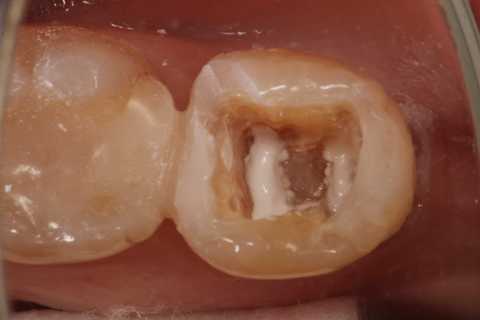

30代女性、左下7、Per、動揺度2.5

今日の症例は8年前に僕が親知らずが遠心に食い込んで虫歯になったものを神経を取らずにCR充填したものだが、とうとう接着剥がれが起こり神経が死んでしまった。神経は全く残っておらず。溶けてなくなっていた。

レントゲン写真では炎症は歯根周囲の歯槽骨に及んでいる。

この症例は歯根内部をいじられていないので、根管治療は難しくない。CRで歯冠を再建するのが難しかった。

再建が終わった後で、内部の治療をしてCRで埋め戻している。